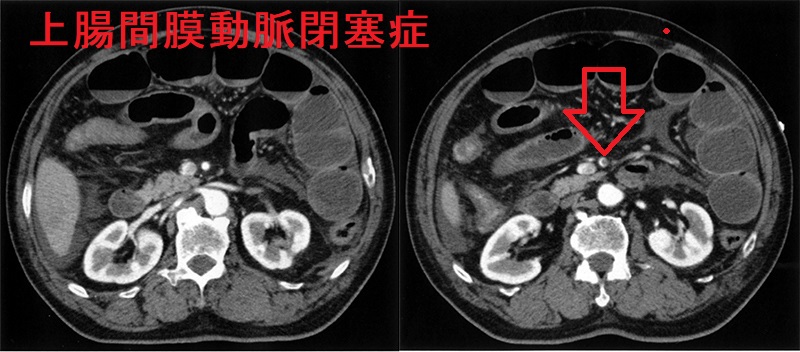

甲状腺機能低下症/潜在性甲状腺機能低下症/橋本病では動脈硬化が進行し、狭心症/心筋梗塞の発症率が上がります(甲状腺と動脈硬化)。全身の動脈硬化の進行は、上腸間膜動脈閉塞症(Acute superior mesenteric artery occlusion:SMAO)に至る可能性があります。

高齢男性で虚血性心疾患(狭心症/心筋梗塞)があり、突然、強烈な腹痛が出現したら、まず上腸間膜動脈閉塞症を疑います。

また、甲状腺機能亢進症/バセドウ病に合併する心房細動(Af)による血栓塞栓症としても発症します。

急性発症で、かつ腸壊死と腹膜炎から腹壁に筋性防御(デファンス)、ショックバイタルを認めたら、上腸間膜動脈閉塞症を疑います。

上腸間膜動脈閉塞症の確定診断は、造影CT検査による上腸間膜動脈の血栓・閉塞の確認です。同時に、麻痺性イレウス、腹水貯留も認めます。

上腸間膜動脈閉塞症では、腸管壊死によりLD(LDH)・CK(CPK)は上昇。腸管壊死による蛋白漏出で低蛋白血症・低アルブミン血症・血管内脱水。DICによる血小板減少・Dダイマー上昇。

上腸間膜動脈閉塞症の治療は

- 腸管壊死前なら血管造影時に血栓溶解薬を投与。改善なければフォガティーカテーテルで血栓除去

- 腸管壊死が疑われたら直ちに緊急開腹手術。上腸間膜動脈バイパス、壊死した腸切除

発症後6時間を超えると、致死率は70-80%で救命困難。